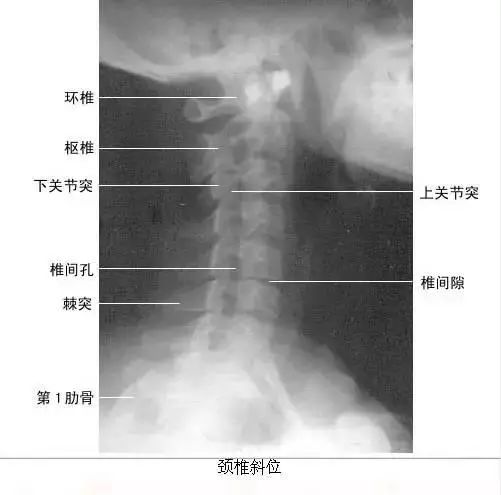

【实用干货】人体体表标志定位与解剖(含人体解剖图)